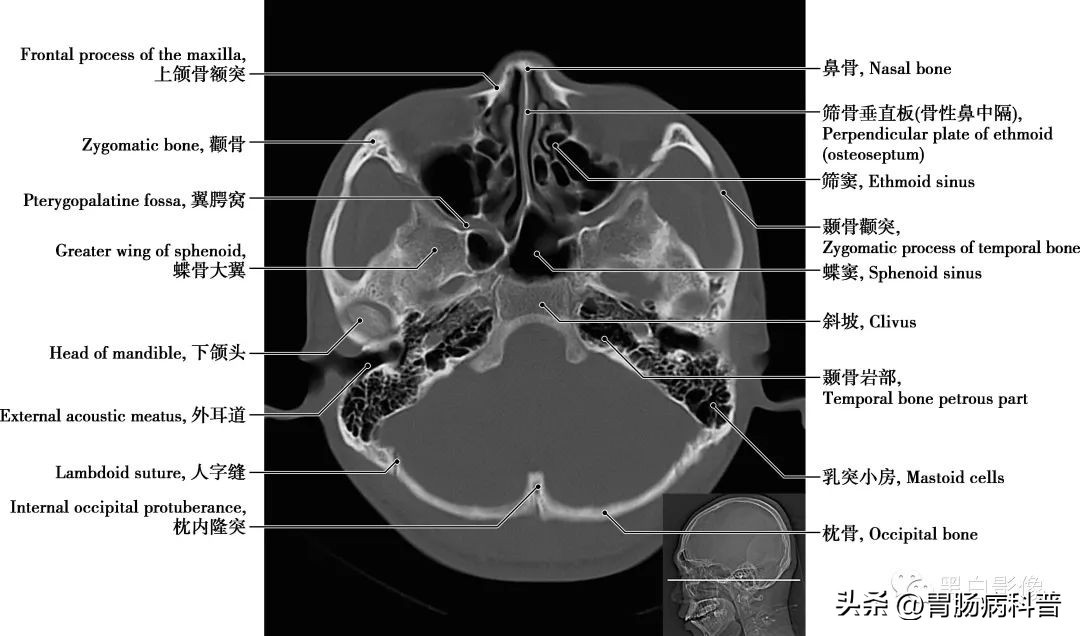

(二)骨窗轴位解剖图

图1-2-18 经下颌头轴位切面

卵圆孔和棘孔 在蝶骨大翼近根部处由前向后可见圆孔、卵圆孔和棘孔,圆孔内走行上颌神经,卵圆孔内走行下颌神经,棘孔内走行脑膜中动脉。颈动脉管 是颈内动脉进入颅腔的管道,在颞骨岩部内弯曲形成一定角度,再经颈动脉管内口于破孔处离开颈动脉管进入颅内